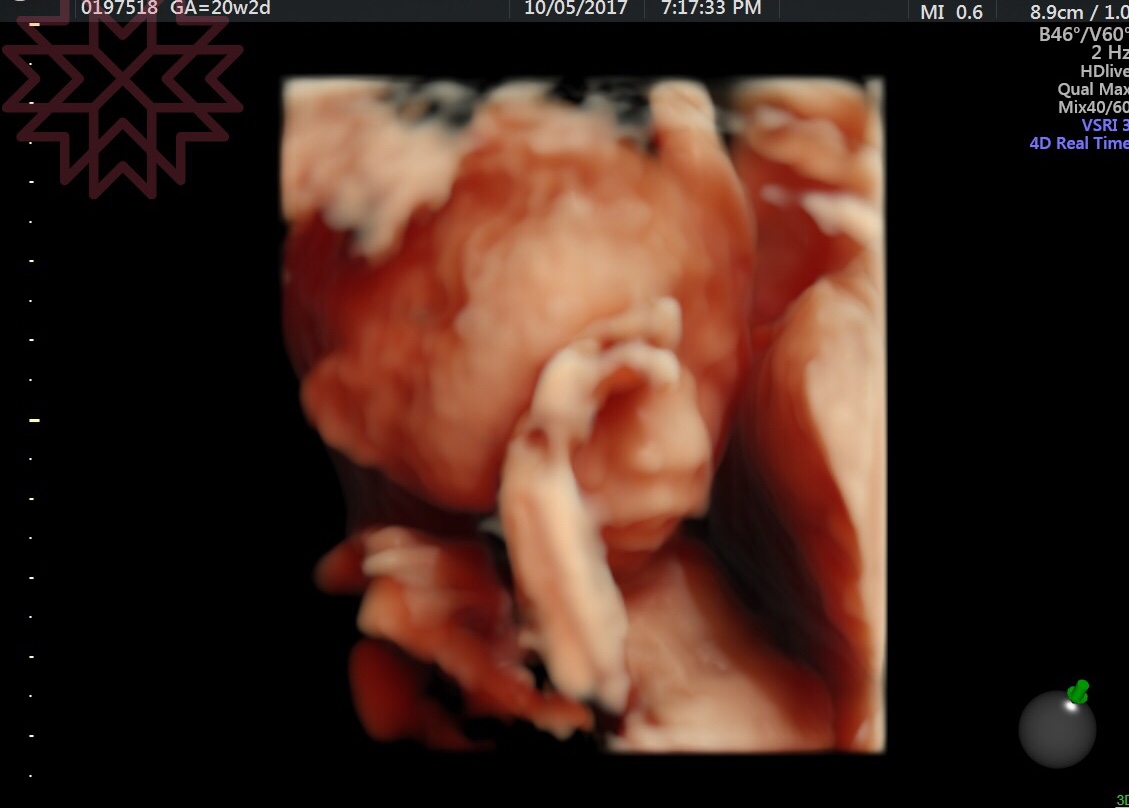

九、4D立體超音波

重要程度:♥

檢查期間:35~37週

自費費用:2,000~3,000

其實這也是高層次超音波的一種,但是這並無實質檢驗的意義,而只是純粹「拍照」,如果你是「記錄狂」、「拍照狂」,或是你已經迫不及待想要看看你即將出生的寶寶長怎樣(這時候面容已發育完畢與出生不會有太大的落差),那記得把寶寶最後留在麻麻肚子記錄下來,將來可以拿出來好好回味一番,必須承認這個商業性質比較大,除非真的有需要不然可以不列入考量。